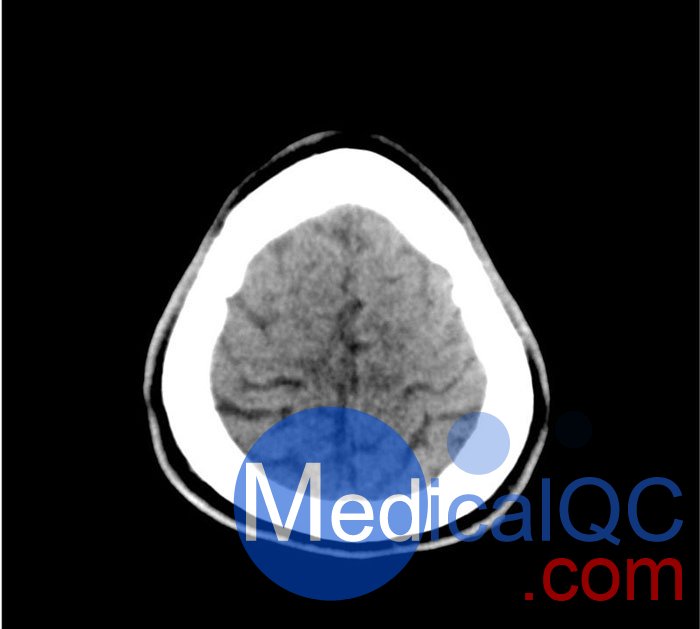

該模型可用于 CT(包括 CBCT)以評(píng)估和優(yōu)化成像性能和 AI 支持的診斷。它也適用于培訓(xùn)目的。

該模型提供了對(duì)常見(jiàn)大腦病理、軟組織和骨組織的詳細(xì)而逼真的模擬??諝饪障短畛溆屑s-160HU的纖維素-聚合物復(fù)合材料。

50-01頭部CT模體,50-01腦中風(fēng)頭部模體,50-01腦出血頭部模體規(guī)格

大?。?約 190 x 210 x 147 mm

重量: 約 2640 g

基材: 纖維素-聚合物復(fù)合材料

最佳管電壓: 120 kVp – 可根據(jù)要求進(jìn)行調(diào)整

產(chǎn)品應(yīng)用:器官分割、圖像質(zhì)量?jī)?yōu)化、中風(fēng)、顱內(nèi)出血

診斷功能:梗塞、出血、血管病變、球形病變

50-01頭部CT模體,50-01腦中風(fēng)頭部模體,50-01腦出血頭部模體影像效果圖: